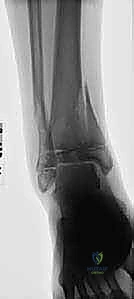

- الأشعة السينية (X-rays): هي الخطوة الأولى والأساسية. يتم التقاط صور من زوايا متعددة (أمامية، جانبية، ومائلة) لتقييم الكسر.

- الأشعة المقطعية ثلاثية الأبعاد (3D CT Scan): تُعد ضرورة حتمية في حالات كسور تيلوكس والكسور ثلاثية المستويات، أو أي كسر يمتد داخل المفصل. توفر الأشعة المقطعية خريطة دقيقة لحجم القطع العظمية ومقدار التباعد (Displacement)، مما يساعد في التخطيط الجراحي المسبق.

- كسور سالتر-هاريس النوع الرابع (Type IV): كسر عمودي يمر عبر الكردوس، ثم لوح النمو، ثم المشاشة وصولاً إلى المفصل. هذا النوع يحمل خطورة عالية جدًا لإغلاق لوح النمو وتكوين جسر عظمي (Bony Bar) إذا لم يتم تثبيته جراحياً بدقة تشريحية مطلقة.

- الكسر ثلاثي المستويات (Triplane Fracture): كسر شديد التعقيد يمر عبر ثلاثة مستويات مختلفة (سهمي، إكليلي، وعرضي). يظهر في الأشعة الأمامية ككسر سالتر-هاريس من النوع الثالث، وفي الأشعة الجانبية ككسر من النوع الثاني. يتطلب هذا الكسر دائمًا فحصًا مقطعيًا (CT Scan) لتقييمه بشكل صحيح.